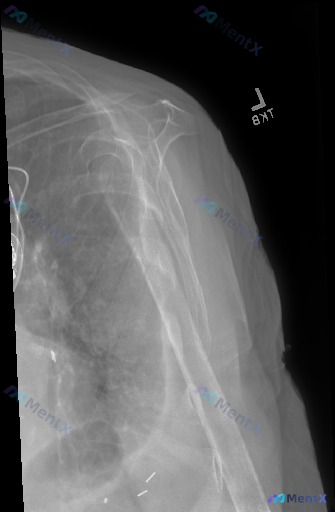

整理到一份左肩部X光正位的病例资料,影像所见比较有讨论点: - 肱骨近端到肱骨干有明显骨折,多发碎骨块,断端移位重叠很显著,肱骨头解剖结构模糊,盂肱关节正常对位已经破坏 - 肩胛骨、锁骨远端(可见部分)、影像内肋骨看起来没有明显骨折脱位 - 肱骨近端和腋下周围软组织肿胀明显,密度增高 - 影像底部有...